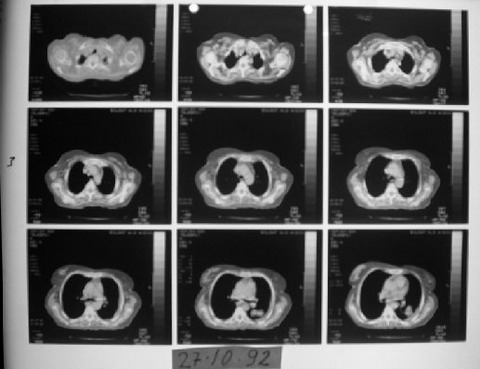

53 yaşında kadın hasta • 9 ayda tam iyileşme

1991 yılında az diferansiye fibröz malign mezotelioma teşhisi konulan 53 yaşındaki kadın hasta, çok düşkün haldeyken immünomodülatör tedavi ile 9 ayda tam iyileşme sağladı. 2000 yılında hasta remisyondaydı ve 9 yıl boyunca hastalık belirtisi göstermedi.

1992 Şubat-Ağustos

Ödem kayboldu, radyoloji normale yakın

1992 Şubat (2. Ay)

Ödem kaybolmuştu, dispne ve taşikardi düzelmişti. İki ay daha aynı tedaviye devam edildi.

1992 Nisan (4. Ay)

Bulgular daha da iyileşmişti.

1992 Ağustos (9. Ay)

Radyolojik bulgular normale yakın hale gelmişti ve immünomodülatör tedaviyi kesmesi önerildi.